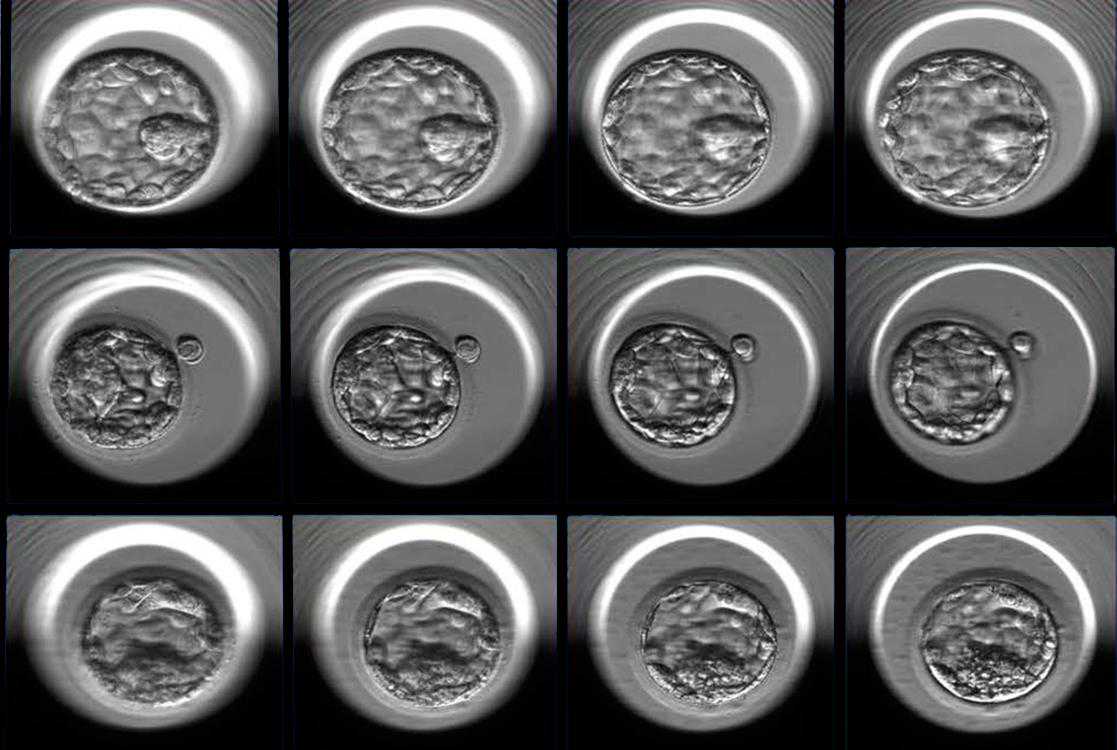

体外人工受孕(简称IVF,Invitrofertilization),就是将卵子与精子取出,在人为操作下进行体外受精,培养成胚胎,再将胚胎植回母体内直至分娩完成的生育过程。利用体外受精技术生产出来的婴儿称为试管婴儿,整个过程真正在试管内的时间只有2-6天而已。

各种原因,都可能导致着床失败。所以如何在IVF过程中筛选出最有可能着床成功的胚胎,就成为了一个最需要解决的问题。

通常的情况是:医生依靠显微镜观察,确定细胞分裂的速率、细胞的对称性以及有关胚胎形态的某些规则表。即便如此,这种方法实现的体外受精的成功率也仅有30%左右。

这个初创公司开发了一种AI算法,可以通过研究积累的成千上万的胚胎数据以及相应的胚胎着床成功率数据,建立一种模型。这种模型就可以用来预测哪些IVF胚胎最有可能着床成功。